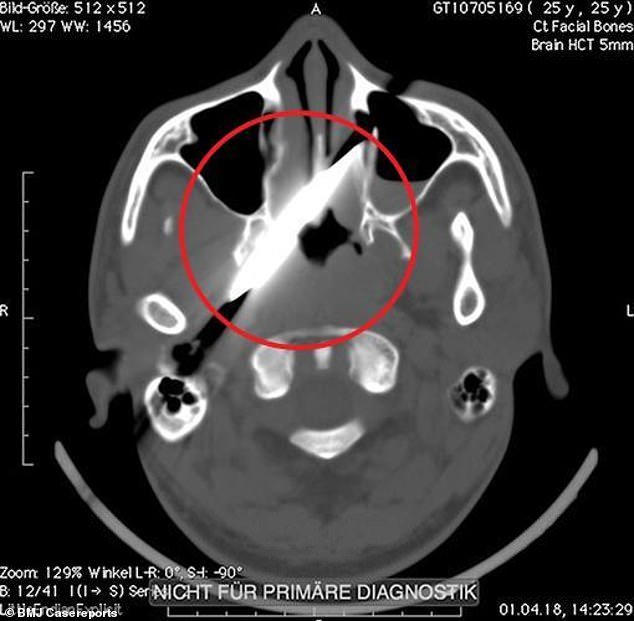

Η μήκους δέκα εκ. λεπίδα είχε καρφωθεί κάτω από το αριστερό μάτι του 25χρονου (Φωτογραφία: BMJ Case Reports)

Η μήκους δέκα εκατοστών λεπίδα που είχε καρφωθεί κάτω από αριστερό μάτι του δεν μπορούσε να μετακινηθεί καθώς είχε σφηνωθεί σε οστό και είχε σπάσει η λαβή του μαχιαριού.